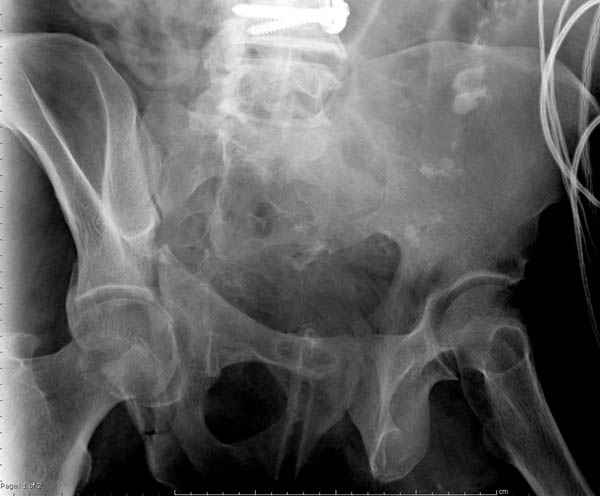

Кроме перелома плеча у больного старый дистракционный перелом T12-L1 оперированный когда-то и кем-то, открытый перелом костей предплечья, который был прооперирован в ночь поступления, после I&D (хирургической обработки). Из-за разрыва селезенки при поступлении травма хирургами произведено удаление.

Дополнительно имеется перелом ацетабулума: задняя

колонна с полупоперечным переломом, и переломы костей лица.

На седьмой день зафиксирован перелом ацетабулума через задний доступ. Перед операцией для профилактики DVT, IVC фильтер, также получает Lovenox.

Извиняюсь за качества снимков, обычный больной в 300 фунтов, портативным ренген аппаратом не пробить.

Очень хорошаая работа, поздравляю! Хотелось бы увидеть снимок таза до операции. Каким образом и как долго предполагаете разгружать тазобедреннй сустав в дальнейшшем?

По возможности вышлите снимки, сканы таза до реконструкции, интраоперационные.

По снимку создается впечатление о высоком поперечном переломе, задней колонны, стенки; почему не пользовались *magic screw*?